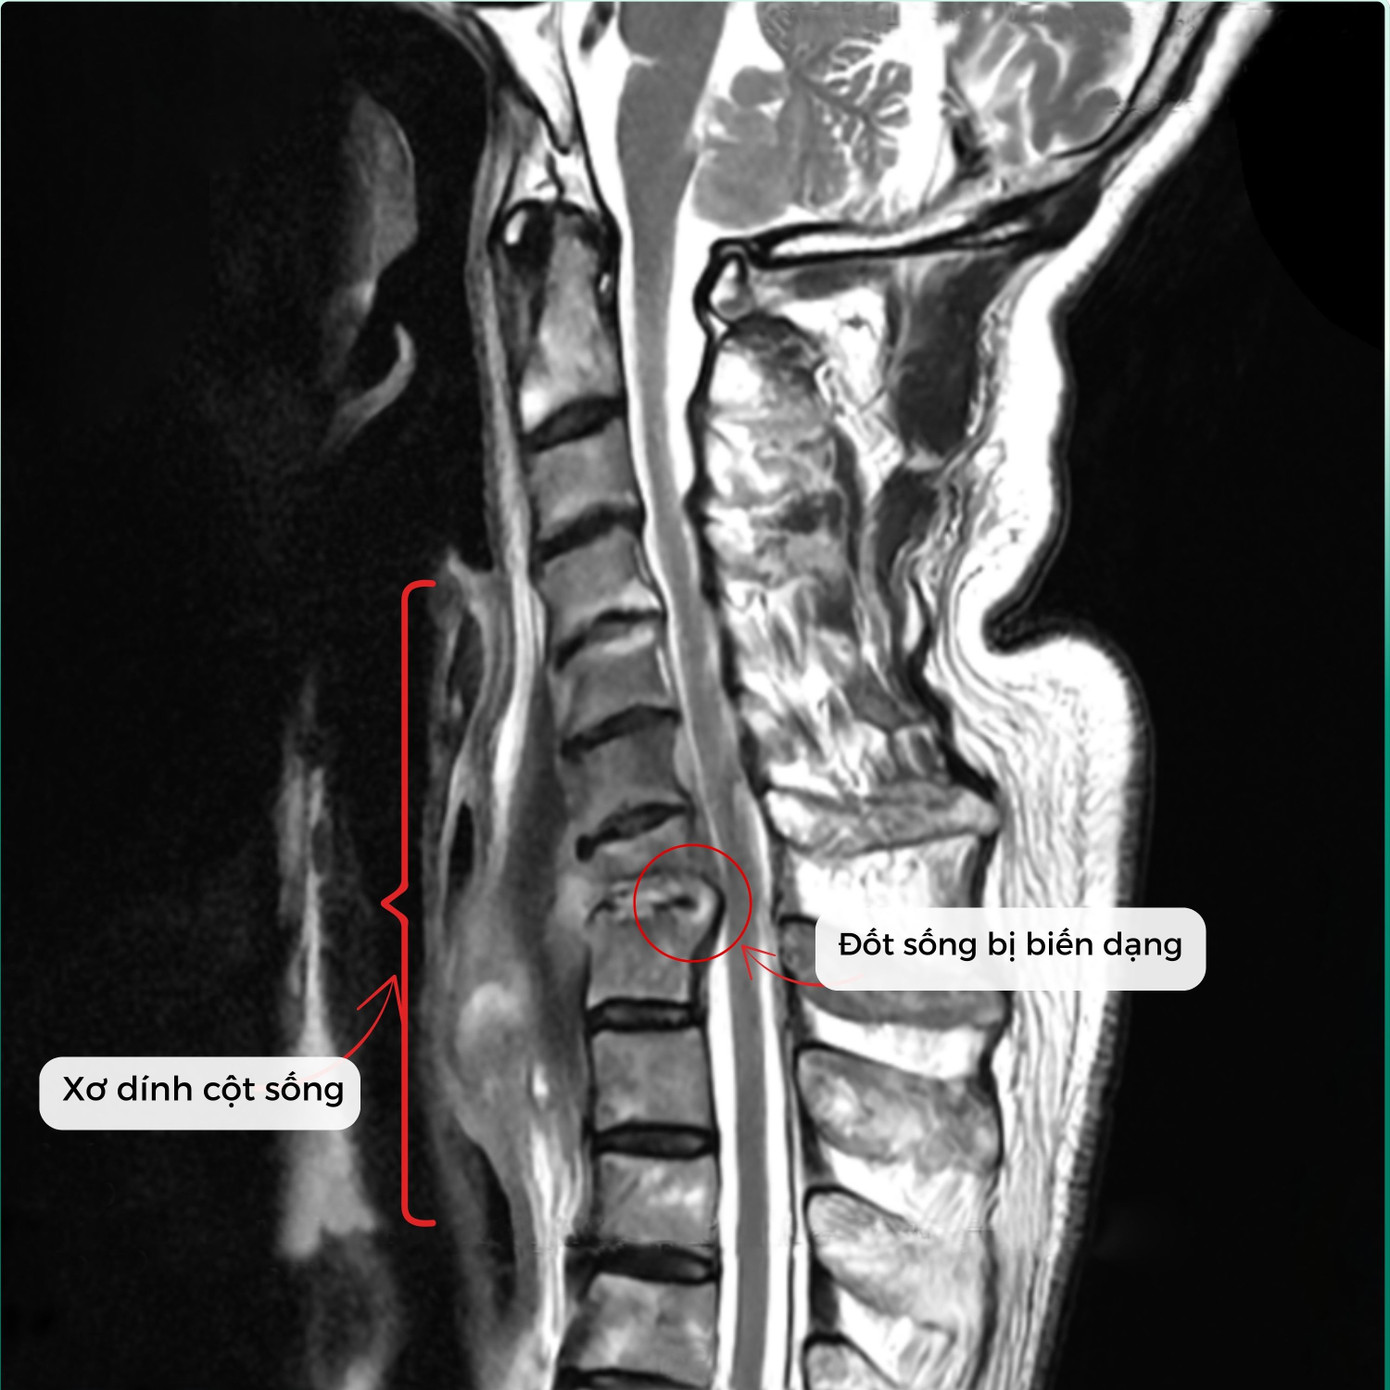

Theo PGS.TS.BS Hà Kim Trung (Chuyên gia phẫu thuật cột sống - Phó Giám đốc Y khoa BVĐK Hồng Ngọc - Phúc Trường Minh) phân tích: Qua kết quả chụp MRI cho thấy bệnh nhân bị nhiễm trùng cột sống cổ. Theo nhiều nghiên cứu y văn trên thế giới đây là tình trạng hiếm gặp, chỉ chiếm khoảng 2 - 7% trong tổng số các ca nhiễm trùng cơ xương khớp. Có thể xuất phát từ chấn thương, biến chứng sau phẫu thuật hoặc lây lan qua đường máu. Tình trạng viêm, áp xe phá hủy thân đốt sống và đĩa đệm C7/T1, tạo dải xơ co kéo khiến cổ bệnh nhân luôn trong tư thế gập, không thể xoay, ngửa. Nếu không phẫu thuật sớm, nguy cơ liệt vận động là rất cao.

Tình trạng xơ dính và đốt sống bị biến dạng trước phẫu thuật